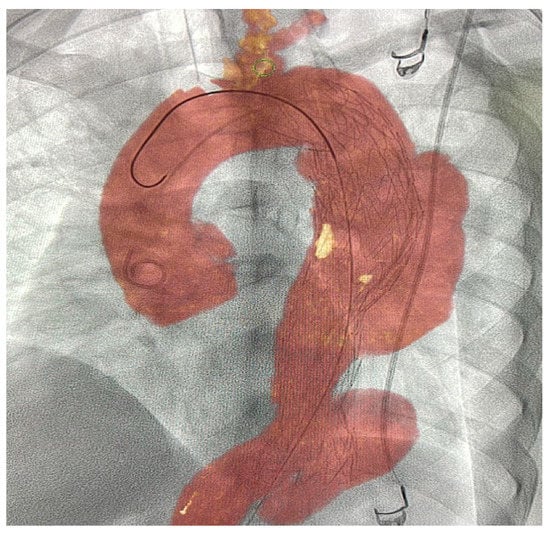

3.4.6. FlightPlan for EVAR

This software is designed to simplify the sizing and planning for EVAR on MRA or CTA. It aids in visualizing vascular anatomy, performing key anatomical measurements, selecting a treatment strategy, measuring endograft size, and saving key information that can be used during an intervention [76]. Moreover, the current software enables zero-click bone removal and CTA tracking of abdominal vessels. It expedites key aorta-sizing measurements and can analyze the endograft-sealing zones. Furthermore, FlightPlan generates and saves the volume, C-arm angulations, and vessel ostia contours to be used periprocedurally. The current version can be used with AW VolumeShare 7 workstations (or higher), Volume Viewer, Volume Viewer Innova, VesselIQ Xpress, AutoBone Xpress, and MR VesselIQ Xpress [76]. Our search revealed no evidence of its practical clinical impact.

Figure 4. Hepatic VCAR software and its role in therapy planning. Color-enhanced 3D volume-rendered images of livers from two patients (a,b) with hepatic malignancies. 3D, three-dimensional; red, hepatic arteries arising from the aorta; blue, hepatic veins leading to the inferior vena cava; gray, portal venous system; green, right-lobe liver parenchyma; purple, left-lobe liver parenchyma. Reprinted from “Comparative analysis of three-dimensional volume rendering and maximum intensity projection for preoperative planning in liver cancer” by Ho et al. [23] with written approval from the corresponding author and publisher (European Journal of Radiology Open; Copyright 2020).